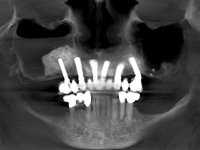

Foi proposto ao paciente fazer uma reabilitação total superior sobre implantes com colocação de uma prótese provisória aparafusada em carga imediata. Após osteointegração seria colocada uma prótese fixa metalo-cerâmica, se possível, com fixação aparafusada. No maxilar inferior foi proposta a colocação de 3 implantes no 4º quadrante para suportar uma ponte metalo-cerâmica de 3 elementos.

Realizada uma TAC, foi planificada a colocação de 6 implantes no maxilar superior. Foi decidida a colocação de dois implantes na zona dos incisivos centrais, dois implantes na zona dos caninos e dois na zona dos segundos pré-molares. A ausência de estrutura óssea na zona distal do primeiro quadrante implicava a realização de uma regeneração óssea no seio maxilar direito. A cirurgia foi realizada e após a colocação dos implantes foi feita a impressão para confeção de uma prótese provisória metalo-acrílica aparafusada para colocação em carga imediata no dia seguinte. O implante colocado na zona do seio maxilar direito não foi colocado em carga. Passados 6 meses foi realizada a impressão aos 6 implantes com técnica de moldeira aberta e foram confecionados os modelos de trabalho. Numa consulta seguinte foram montados os modelos de trabalho em articulador semi-ajustável utilizando o arco facial e a relação inter-maxilar obtida com a prótese provisória. Foi feita uma muralha de silicone sobre a ponte provisória com o objetivo de orientar o trabalho laboratorial. Realizada a infra estrutura metálica aparafusada esta foi provada em boca e finalmente após colocação de cerâmica o trabalho foi colocado definitivamente. Como passaram vários meses após a realização da primeira TAC foi feita uma segunda para planificar a colocação de implantes no 4º quadrante. Colocaram-se 3 implantes na mesma sessão em que foi feita a extração dos pilares da ponte. Estes implantes foram posteriormente reabilitados com uma ponte metalo-cerâmica aparafusada de três elementos.